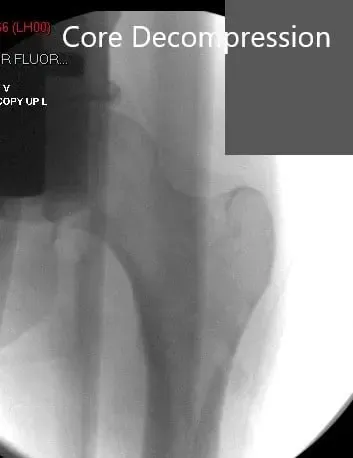

Jamshidi needle was inserted into the left iliac crest and about 180 ml of fluid was aspirated. The aspirate was processed using the harvest system. The two guidewires were then placed into the left hip under fluoroscopic control in a percutaneous manner. Core decompression was performed at the location of the avascular necrosis.

Core Decompression at the site of avascular necrosis.